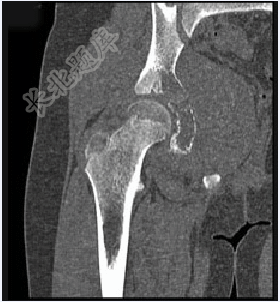

- 单项选择题男,15岁,右髋部疼痛、红肿,有压痛,皮温增高,结合图像,最可能的诊断是( )

A、Ewing肉瘤

B、急性骨髓炎

C、转移性神经母细胞瘤

D、骨肉瘤

E、骨结核